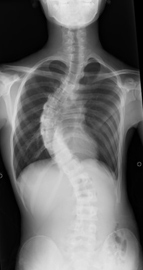

骨軟部腫瘍は比較的まれな疾患ですが、有名な骨肉腫(骨の癌)などは10歳代から20歳代の若年者の膝周囲に多く発症し、初期治療を誤ると死に至る病気です。現在は医療技術の進歩により早期に見つかれば下肢を切断することもなく、5年生存率は70%以上となりました。ただし、早期に見つけることが重要です。

当院ではレントゲン、また最新のMRIによって的確に早期に診断することができます。